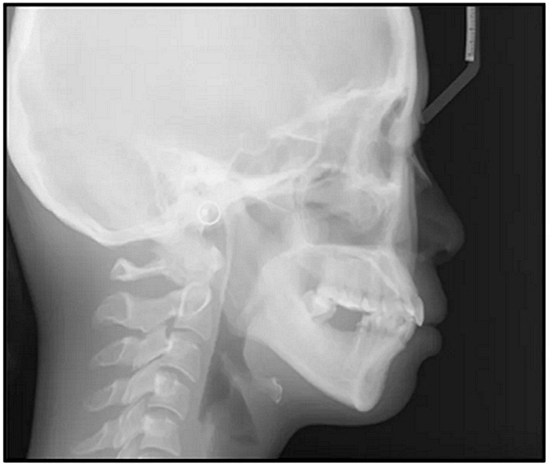

總之,這種復(fù)合錯(cuò)合畸形是一個(gè)很?chē)?yán)重的問(wèn)題,需要進(jìn)行認(rèn)真的多學(xué)科序列治療。治療后X光片(圖6)和重疊頭影測(cè)量圖(圖7)記錄了跨學(xué)科治療結(jié)果。

圖5. 治療前的側(cè)位片(上圖)和全景(下圖)的X光片